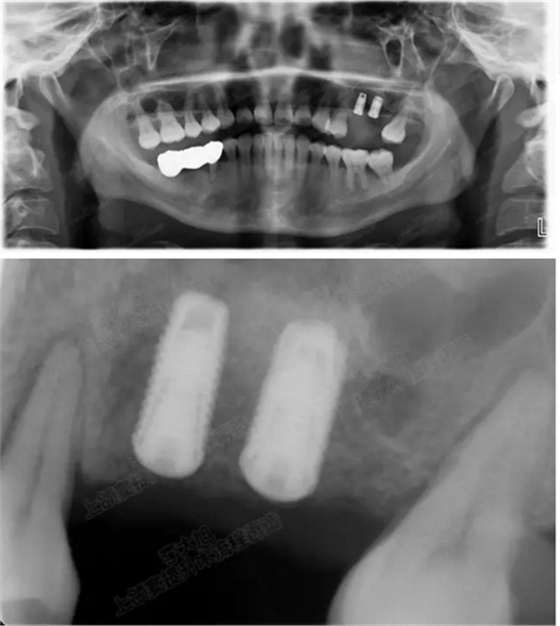

修復(fù)后一年

002.png

病例二

剩余骨量2mm

003.png

提升10mm